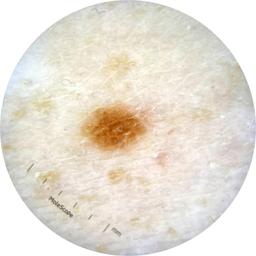

ISIC_9785574

Information

2003 x 2003

MEL-SELF Trial, https://www.sydney.edu.au/medicine-health/our-research/research-centres/melself-project.html

Field Value

acquisition_day 148

age_approx 45

anatom_site_1 Head and neck

anatom_site_general head/neck

concomitant_biopsy False

diagnosis_1 Benign

diagnosis_confirm_type single image expert consensus

family_hx_mm True

image_manipulation instrument only

image_type dermoscopic

lesion_id IL_0236417

patient_id IP_8456088

personal_hx_mm True

sex female